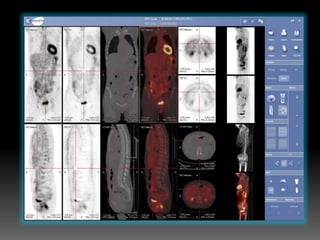

SPECT/CT - desenvolvida por HALL ANGER em 1960. Um colimador e chumbo é usado entre paciente e

o detector para eliminar raios gama que não tenham direção perpendicular a ele (O que torna a

imagem com uma melhor resolução). As imagens são produzidas com o auxílio de um computador

se funde entre a tomografia por emissão de pósitron e à tomografia computadorizada, podendo

detectar alterações menores, a tomografia computadorizada informa riqueza de detalhes anatômicos

e a medicina nuclear informa dados fisiológicos desta forma esta modalidade permite estudos da

anatomia e fisiologia. Podendo destacar nas especialidades de oncologia (para planejamento

SPECT/CT - desenvolvidapor HALL ANGER em 1960. Um colimador e chumbo é usado entre paciente e o detector para eliminar raios gama que não tenham direção perpendicular a ele (O que torna a imagem com uma melhor resolução). As imagens são produzidas com o auxílio de um computador integrado no equipamento.

se funde entrea tomografia por emissão de pósitron e à tomografia computadorizada, podendo detectar alterações menores, a tomografia computadorizada informa riqueza de detalhes anatômicos e a medicina nuclear informa dados fisiológicos desta forma esta modalidade permite estudos da anatomia e fisiologia. Podendo destacar nas especialidades de oncologia (para planejamento radioterápico) neurologia e cardiologia.